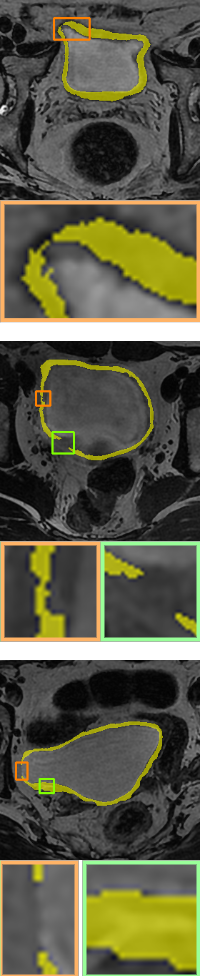

In this section, we will add two different topological energies to Topo-NLSTD model Eq. 13. For convenience, when adding energy without width information Eq. 11, it is denoted as PH; when adding width-aware topological energy Eq. 12, it is denoted as WT. Fig. 7, Fig. 8 and Fig. 9 show the results on synthetic images, the International Symposium on Image Computing and Digital Medicine (ISICDM) 2019 dataset [isicdm] and the Massachusetts Roads dataset [mass], respectively. From the results, we can see that NLSTD retains more image information compared to STD rather than performing a simple smoothing. Then, the results of PH are usually connected to a single-pixel width line or a single-pixel genus to satisfy a given topological constraint. In contrast, our proposed energy not only maintains the topological consistency well, but also fuses the width information.

Image

UNet[unet]

STD[std]

NLSTD[densecrf]

PH[ph]

Proposed WT